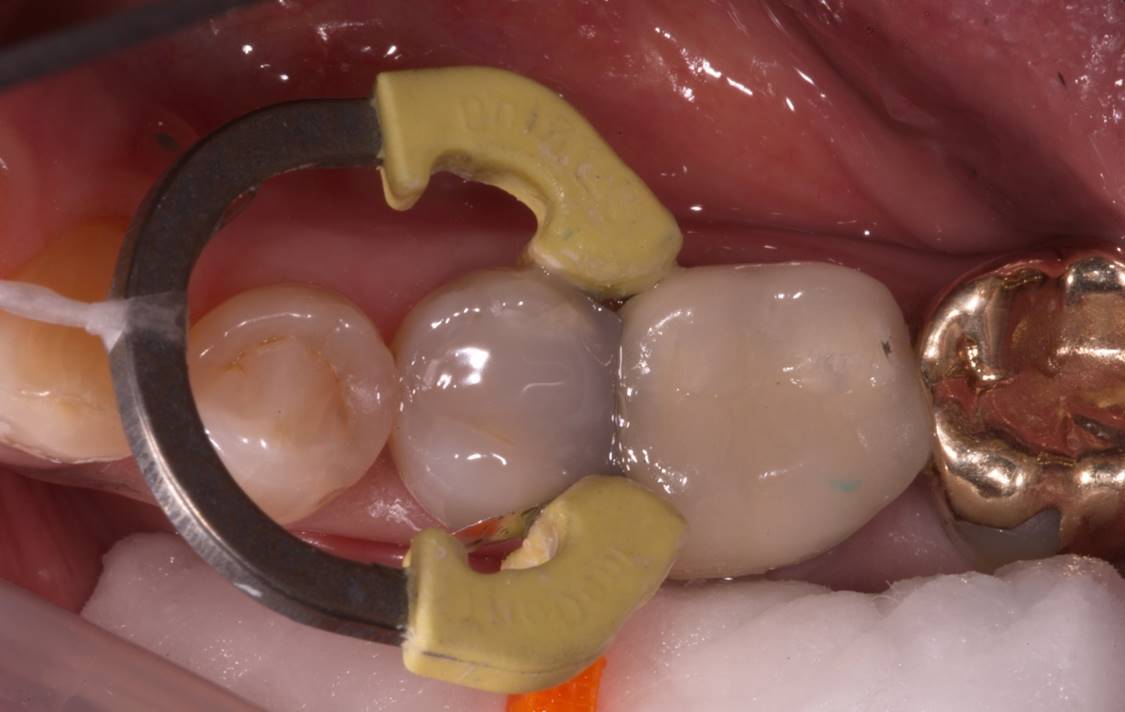

Fig 14. The defective restoration was removed; a sectional ring was placed to ensure good, tight contact when placing the lower viscosity bulk fill, as well as ideal separation of tooth structure for proper adaptation; glass ionomer was placed for pulpal protection.

Figure 14